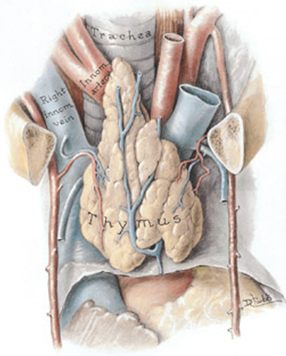

Mediastinit divararalığı toxumasının iltihabı xəstəliyidir, kəskin və xroniki formada ortaya çıxa bilir.

Kəskin mediastinit divararalığı toxumasının irinli iltihabı xəstəliyi olub, əksər hallarda döş qəfəsi orqanlarındakı zədələnmələrin, boyun və qarın boşluğundakı iltihabın yayılması nəticəsində ikincili olaraq meydana çıxır. Adətən sepsisə səbəb olur və vaxtında müalicə olunmazsa yüksək letallığa gətirib çıxarır.

Xroniki medisatinit isə divararalığının qranulomatoz iltihabı və fibrozu olub, adətən xroniki iltihabi xəstəliklərin (infeksion və digər) nəticəsində meydana gəlir.